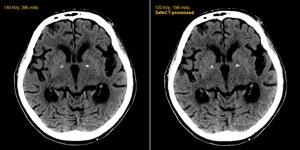

January 5, 2011 — The U.S. Food and Drug Administration (FDA) has given clearance for Medic Vision Ltd. to market its ...

Computed tomography (CT) offers a very important, noninvasive diagnostic tool, but the price of high image quality ...